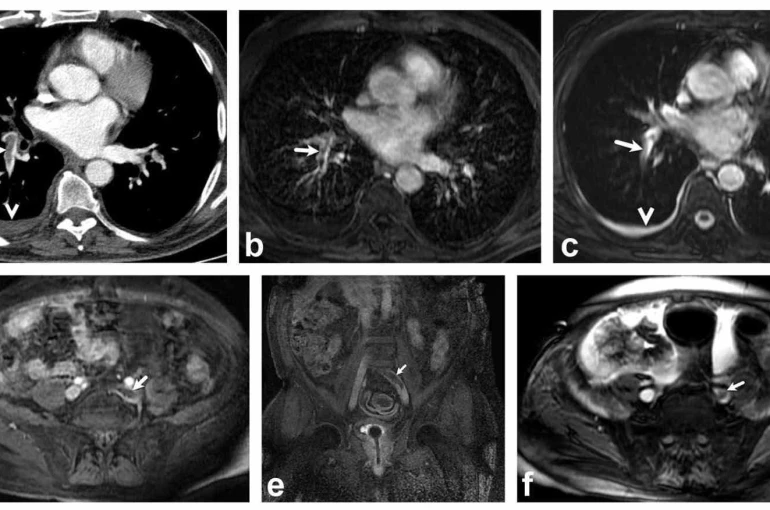

Bir dönem Denizli Tekden Hastanesinde de çalışan ve çalışmalarına ABD’de devam Dr. Nevzat Karabulut ve ekibinin yaptığı, British Journal of Radiology dergisinde yayımlanan "Diagnostic performance of contrast-enhanced and unenhanced combined pulmonary artery MRI and magnetic resonance venography techniques in the diagnosis of venous thromboembolism" başlıklı araştırmada manyetik rezonans (MR) yöntemi kullanılarak hem akciğer damarlarının hem de pıhtının kaynağı olan bacak toplardamarlarının aynı anda, tek bir incelemede değerlendirilebileceği gösterildi. Toplam 44 hastanın incelendiği çalışmada elde edilen sonuçlar oldukça dikkat çekti.

Kontrastlı MR yöntemi, hastaların tamamında akciğer embolisini doğru şekilde tespit ederken; kontrastsız MR yöntemi de yüksek doğruluk oranına ulaştı ve önemli ölçüde güvenilir sonuçlar verdi. Bu bulgular, radyasyon içermeyen MR yönteminin pıhtı hastalığını saptamada güçlü bir alternatif olduğunu ortaya koydu. Özellikle Radyasyon riskinin daha önemli olduğugenç hastalarda ve gebelerde MR’ın güvenli ve etkili bir seçenek olabileceği vurgulandı.